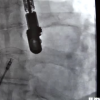

80 yaşına kadar delik kalple yaşayan hasta, başarılı bir operasyonla sağlığına kavuştu. Malatya'da 80 yaşındaki Hasan Örnek'in, kalbinde doğuştan delik olduğu, yorgunluk ve nefes darlığı şikayetiyle başvurduğu hastanede fark edildi. Örmek'in tetkiklerinde kalbinde doğuştan gelen 1,8 santim büyüklüğünde delik olduğu tespit edilince Kardiyoloji Uzmanları Prof. Dr. İzzet Tandoğan ve Uzm. Dr. Sezai Orhan tarafından ameliyata alındı. Kapalı yöntemle geçirdiği ameliyat sonrası yaşlı hasta yeniden eski sağlığına kavuştu.

Kardiyoloji Uzmanı Prof. Dr. İzzet Tandoğan, hastada bir anormallik saptadıklarını belirterek "Kalbin içerisindeki delik, normalde anne karnındayken olabilen fakat doğuma kadar kapanan bir deliktir. Normal şartlarda biz böyle hastalarla karşılaşıyoruz ama 10 ya da 20'li yaşlara kadar karşılaşıyoruz. O yaşlara kadar bu hastalar tedavi edilmemişse kalp yetmezliği başlıyor. Hastamızın 80 yaşına kadar kalbindeki delikle yaşaması bir hayli ilginç. Biz, 80 yaşındaki bir hastamıza ilk defa bu işlemi uyguladık. Çünkü ilk defa 80 yaşında ve kalbi bir delik hasta gördük. Başarılı bir operasyonla hastamız sağlığına kavuştu" şeklinde konuştu. Kardiyoloji Uzmanı Sezai Orhan ise hastanın yaşının ilerlemiş olması nedeniyle nadir görülen bir durumla karşı karşıya kaldıklarını söyleyerek "Gerçekten başarılı bir işlem uyguladık. Operasyon komplikasyonsuz uygulandı. Hocamızın ve ekibinin ellerine sağlık" ifadelerine yer verdi. Örnek'in oğlu Vakkas Örnek ise "Ben yurt dışında yaşıyorum. Malatya'da böyle bir ameliyatın olacağını düşünmemiştim. Yurt dışında bile böyle bir ameliyatı göze alabilecek doktorlar çok nadir bulunur. Doktorlara, yönetimine ve çalışanlarına teşekkür ediyorum" diye konuştu. Geçirdiği operasyonla sağlığına kavuşan Hasan Örnek'de durumunun şuan iyi olduğunu dile getirerek doktorlarına teşekkür etti.